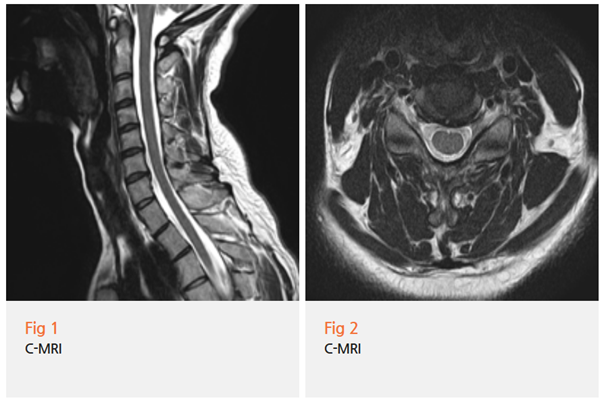

저는 일단 정밀 검사부터 진행했습니다.

✔️ 경추 MRI - 목디스크 위치와 정도 확인

✔️ 상지 근전도 검사 - 신경 손상 여부와 위치 파악

✔️ 자율신경계 검사 - 신경병증성 통증 동반 여부 확인

그리고 결과를 보는 순간, '역시' 싶었습니다.

MRI상으로는 목디스크가 있긴 한데 생각보다 심하지 않았어요.

근데 문제는 근전도 검사에서 나왔습니다.

경추 5번, 6번 신경근에 급성 신경근병증이 확인된 거예요.

쉽게 말하면, 디스크 자체는 심하지 않은데

그 디스크가 눌러서 생긴 '신경 손상'이 상당히 진행된 상태였던 겁니다.